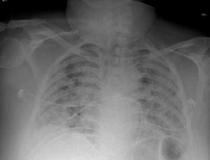

This photo gallery shows the variety of radiological presentations of COVID-19 (SARS-CoV-2) in medical imaging, including computed tomography (CT), radiograph X-rays, ultrasound, echocardiograms and magnetic resonance imaging (MRI). The radiology images show examples of typical COVID pneumonia in the lungs and the numerous complications the virus causes in the body in multiple organs, including the brain, kidneys, heart, abdomen and vascular system.

Ultrasound, especially hand-held ultrasound imaging devices, have become a primary imaging modality for novel coronavirus because of the ease to bag the device and sterilize it after use. CT and mobile X-ray systems are also used as front-line imaging systems for COVID-positive or suspected COVID patients.